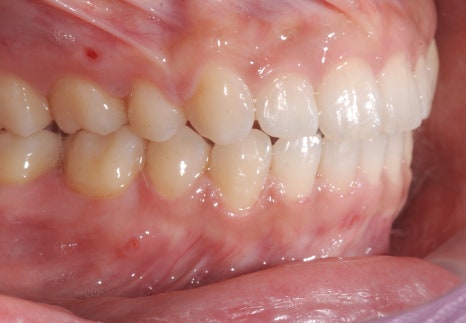

<Before-and-after orthodontic treatment photos>

Treatment period: 23.01.18 - 24.6.04 (about 1 year and 6 months)

Treatment performed: protrusion, midline improvement